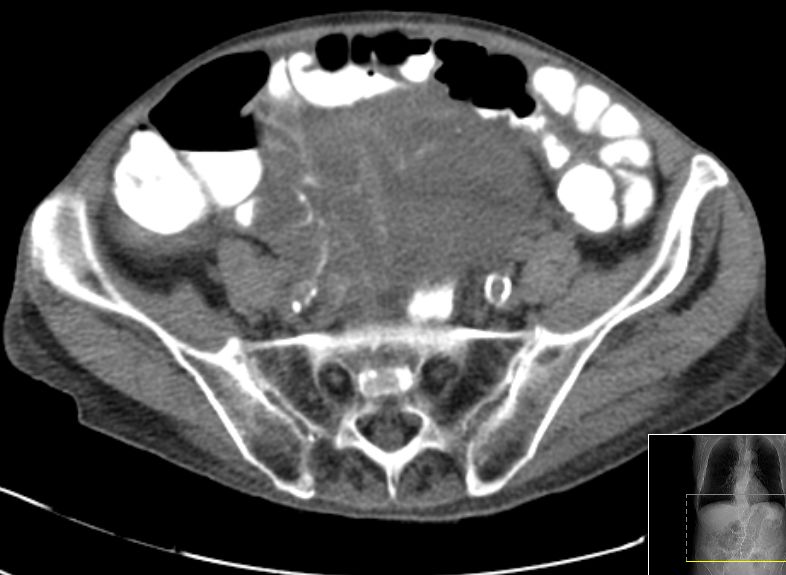

71-jährige Frau mit Adenokarzinom der Appendix pT4b pNo Mo Lo Vo.

Coloskopie: zirkuläres, exophytisch und ulzerierend wachsendes Karzinom mit einer Größe von 60 mm im Colon ascendens, nicht passierbar.![]() |

![]() |

Unmittelbar oberhalb der Ileozökalklappe Nachweis eines 7 x 6 cm großen, schüsselförmig exulzerierten Tumors.

Der Tumor durchdringt alle Wandschichten und infiltriert retrograd den davor geschalteten Dünndarm.![]() |